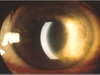

Ved undersøkelsen finner du at pasienten har ciliær injeksjon.

Ciliære injeksjoner, dypere inflammasjon i øyets kar, er assosiert med tilstander som akutt iridocyklitt, keratitt og akutt glaukom. Dette er synstruende tilstander som trenger behanding.

Hva er kort karakteristikka for iridocycklitt?

Regnbuehinnebetennelse.

- En form for uveitt; uveitt omfatter iris, corpus ciliare og årehinnen.

- Skilles ellers mellom fremre, bakre og kombinert uveitt.

Debuterer akutt. Medfører ubehag, smerter, nedsatt syn, rødt øye, tåreflod, lysskyhet. Debuterer som regel unilateralt.

Det er ikke nødvendigvis smerte tidlig i forløpet.

- Liten pupille/ bakre synekier. Diagnostisk dilatasjon

- Affiserer oftest personer i aldersgruppen 20-40 år

- Krever rask behandling. Diagnose og behandling hos øyelege.